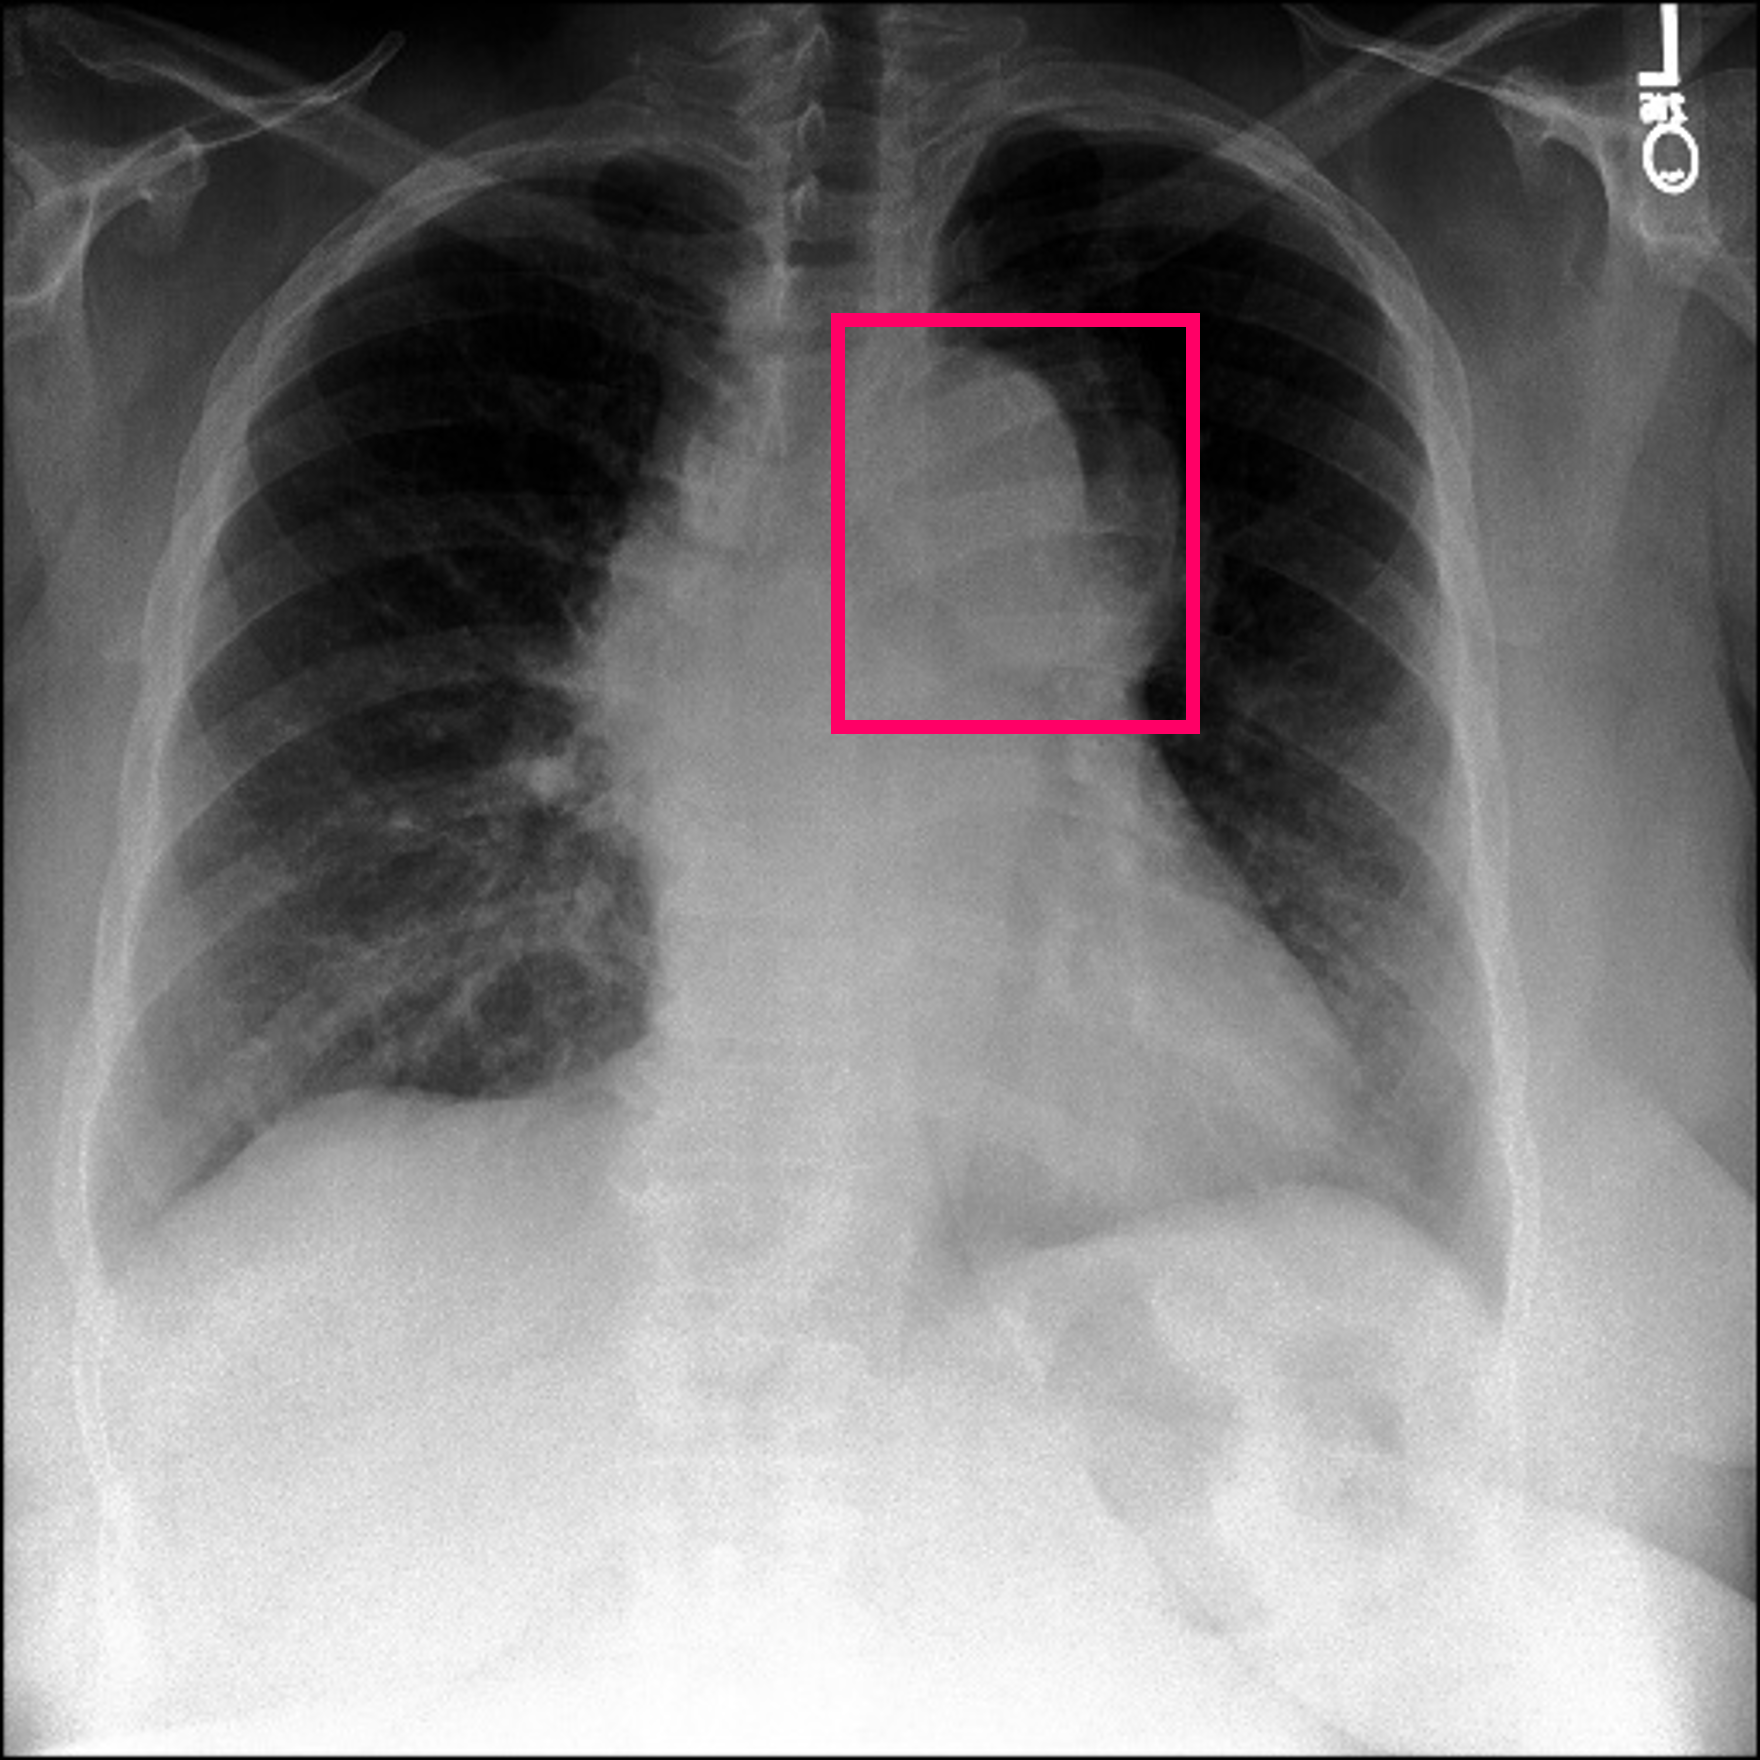

3.3 Interpretability

Post-Hoc Comparisons. We compare our concept-based explanations to post-hoc XAI techniques LIME and SHAP, applied to the baseline InceptionV3 model. The image explanations generated by these techniques disagree with each other and the medical ground truth. We show an example of this observation in Figure 7, where both techniques fail to capture the large mass in the X-ray, and highlight irrelevant regions such as areas outside of the lung as incorrectly important to the classification decision. In contrast, our approach correctly identifies the presence of a mass. More examples are shown in Figure 10.

Refer to caption

(a) Ground Truth

(b) LIME

(c) SHAP

(d) CXR-LLaVA Generated Report

(e) Our Approach

Figure 7: Example of our explanation approach outperforming LIME, SHAP and CXR-LLaVA. Ground truth (a) is a “Large right upper zone mass". LIME (b) and SHAP (c) fail to capture the mass in the X-ray. Most important image regions are bounded by yellow for LIME, and shown in more vibrant green for SHAP. CXR-LLaVA (d) generates a report which wrongly describes the image as non-cancerous. Our approach (e) correctly identifies the presence of a mass.